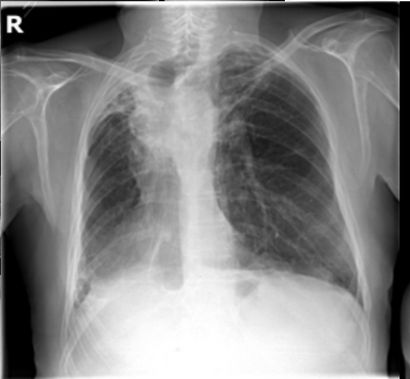

The evaluation of infectious disease processes on radiologic images is an important and challenging task in medical image analysis. Pulmonary infections can often be best imaged and evaluated through computed tomography (CT) scans, which are often not available in low-resource environments and difficult to obtain for critically ill patients. On the other hand, X-ray, a different type of imaging procedure, is inexpensive, often available at the bedside and more widely available, but offers a simpler, two dimensional image. We show that by relying on a model that learns to generate CT images from X-rays synthetically, we can improve the automatic disease classification accuracy and provide clinicians with a different look at the pulmonary disease process. Specifically, we investigate Tuberculosis (TB), a deadly bacterial infectious disease that predominantly affects the lungs, but also other organ systems. We show that relying on synthetically generated CT improves TB identification by 7.50% and distinguishes TB properties up to 12.16% better than the X-ray baseline.